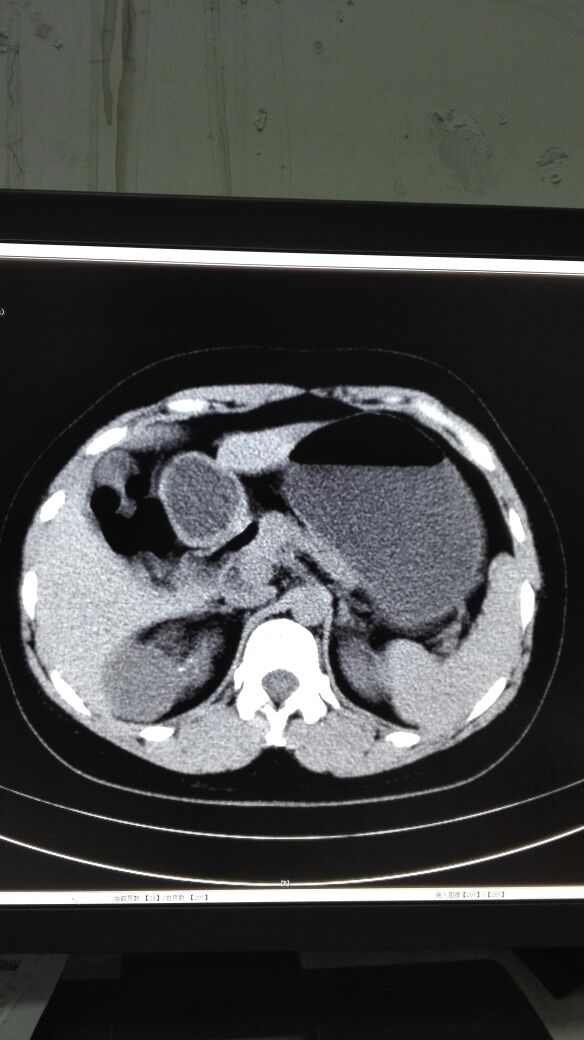

患者女,40岁,医院职工家属。B超体检时发现肝肾间多发囊性占位性病变。行腹部平扫示:右肾上腺区囊性占位,有分割和钙化点,右肾受压下移。诊断意见:右肾上腺囊腺瘤可能性大,建议进一步检查明确。后到市级医院检查并切除手术,病理切片考虑肾上腺囊肿。今腰部不适复查CT片。